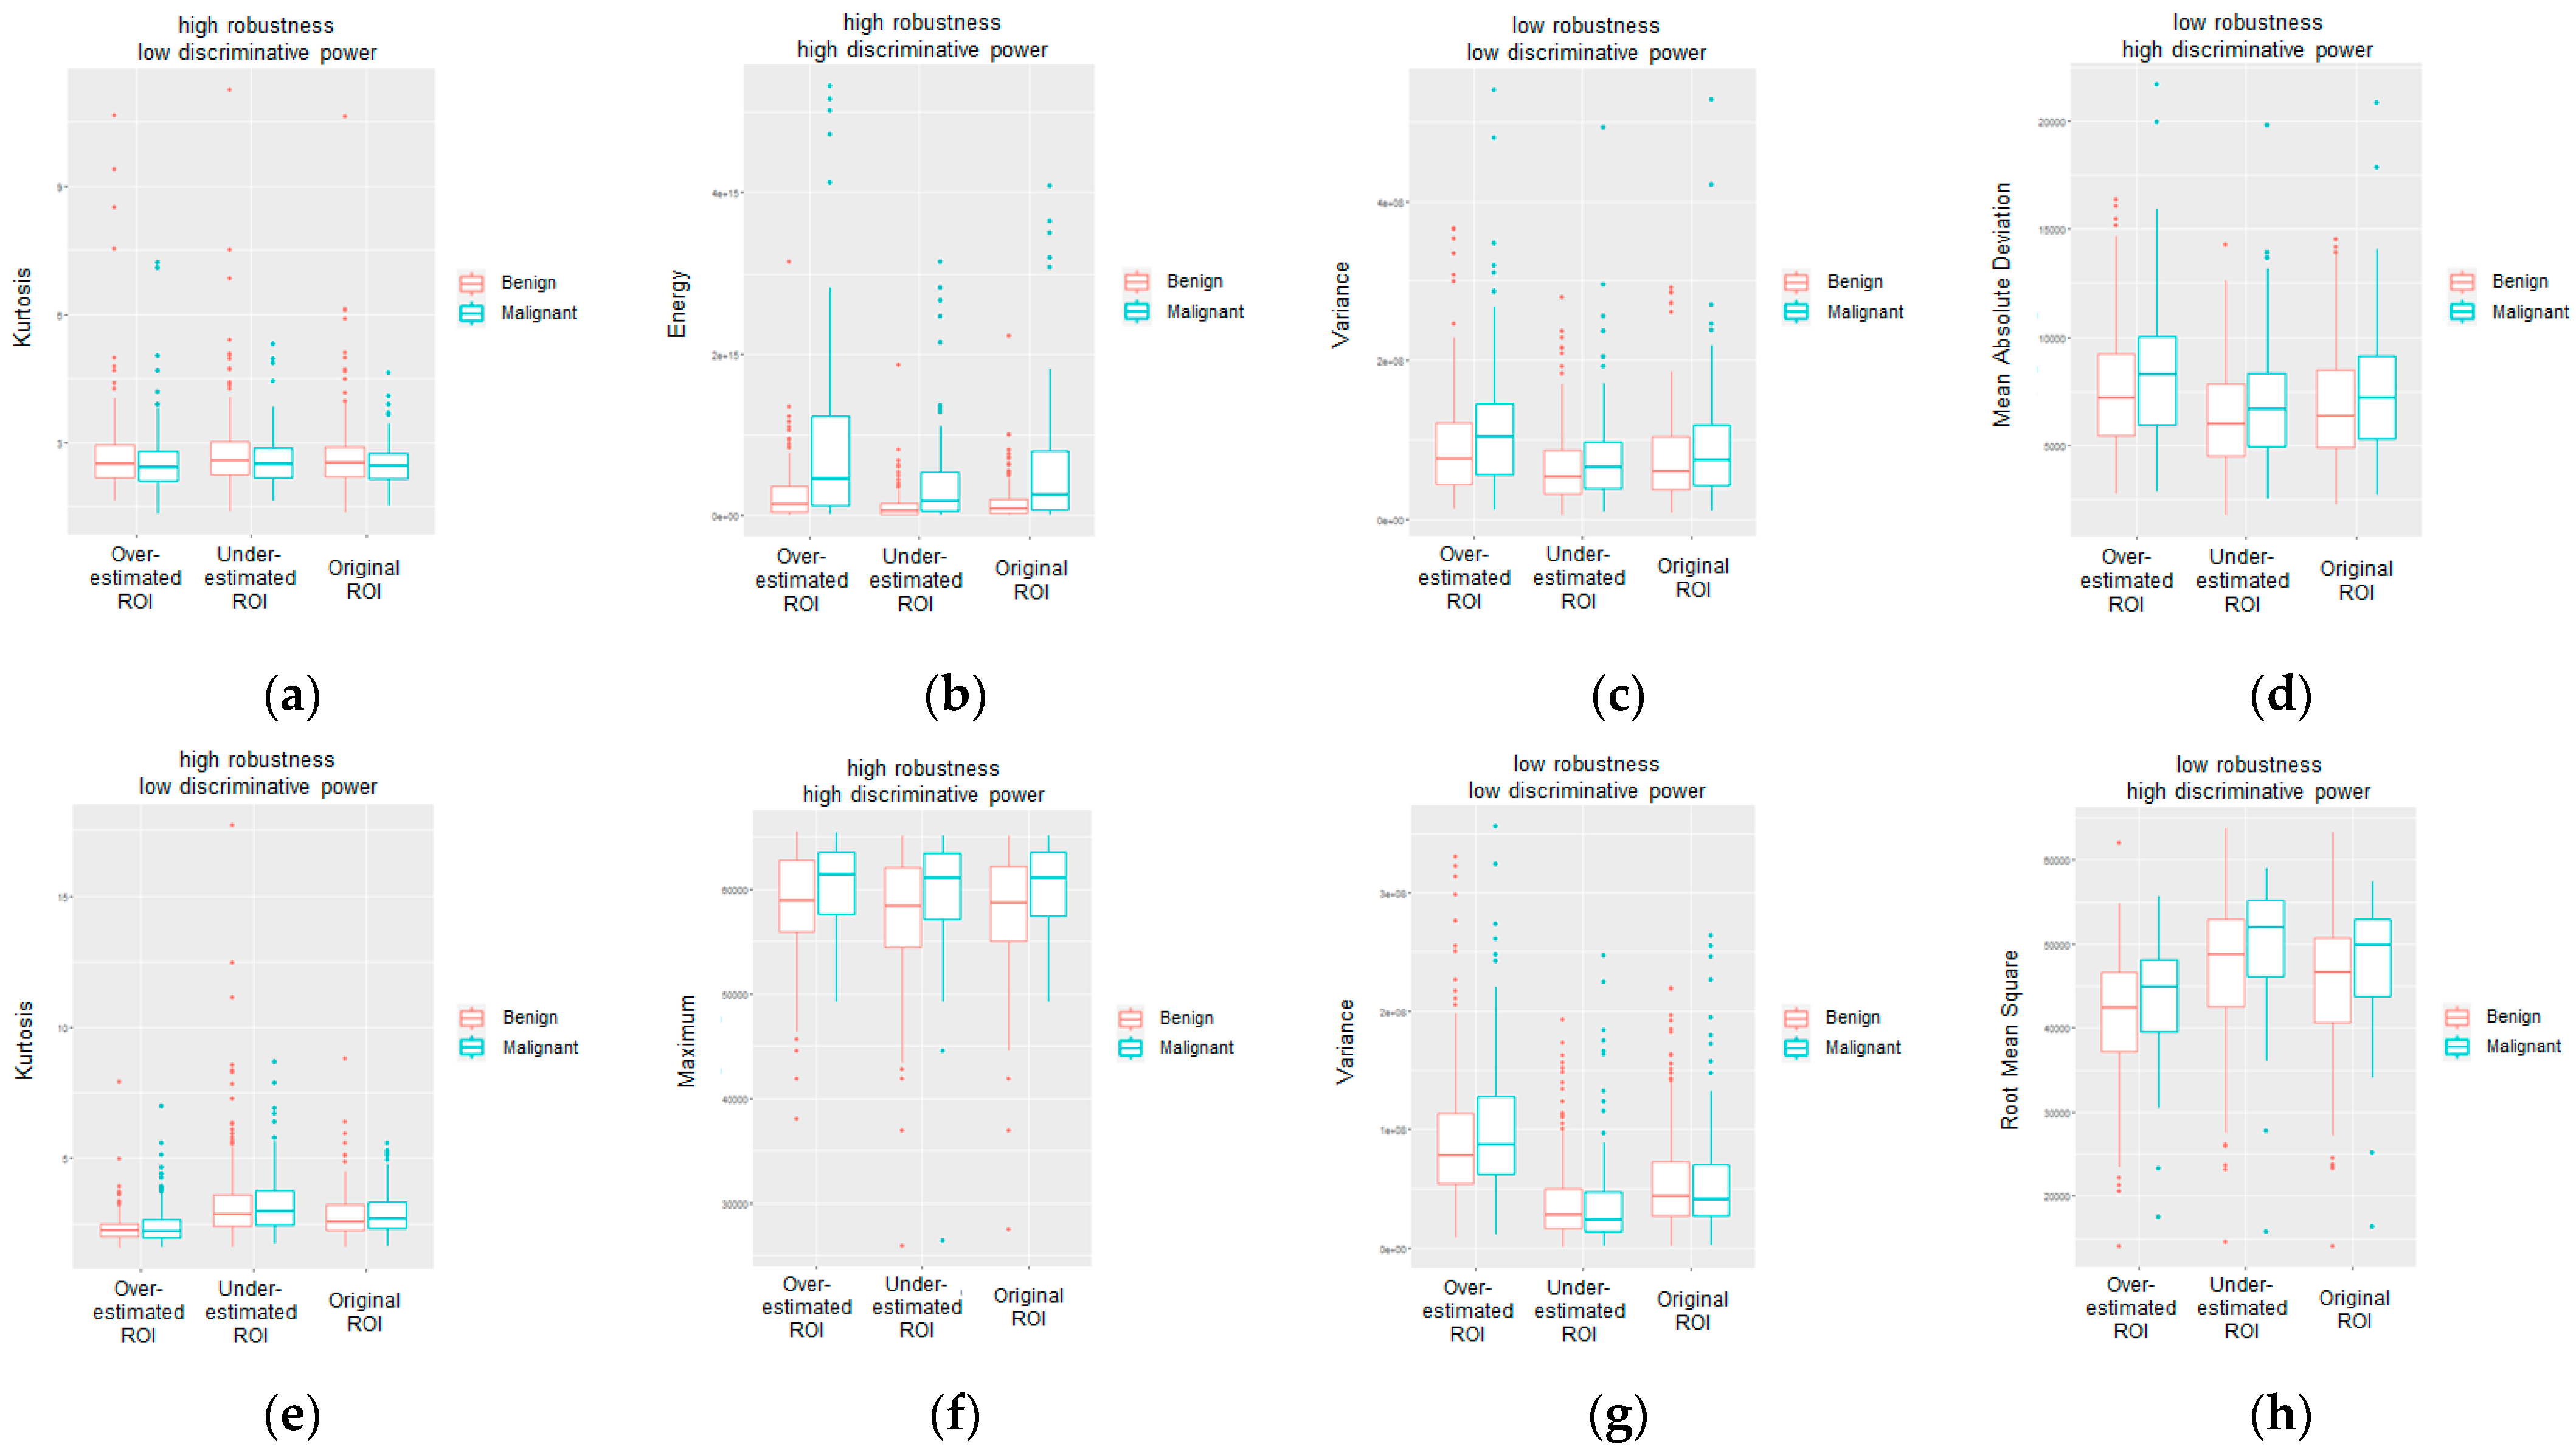

3. Results

4. Discussion